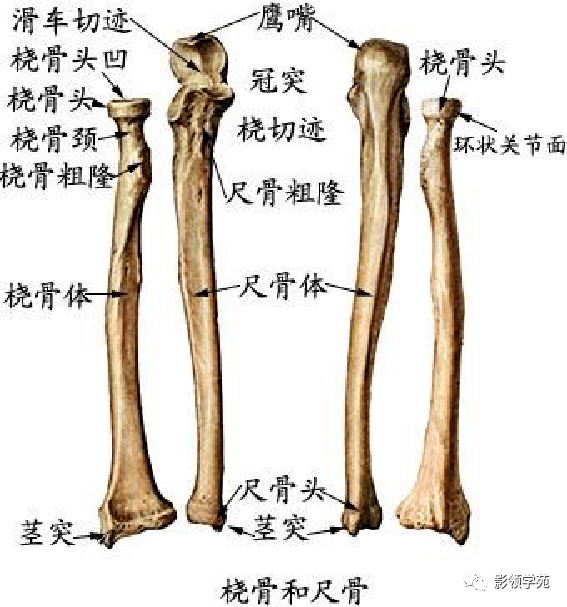

骨骼系统

骨骼系统